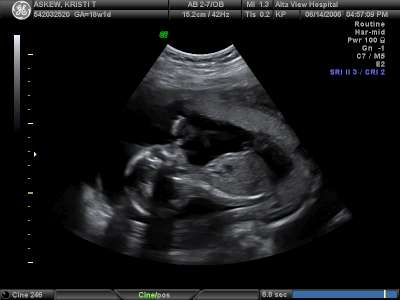

Thumb's up!

She's giving mom and dad a thumb's up letting us know she's doing well in there!